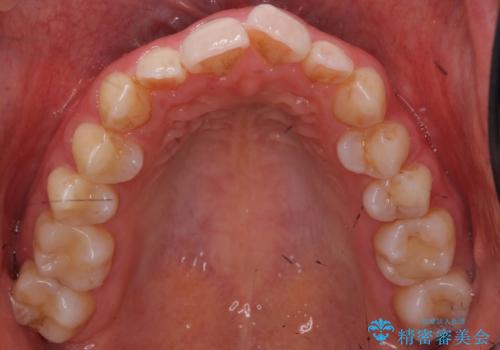

歯の着色を落としたい

- 表面の着色を気にされて、ご来院されました。

お話しをしたところ、リーズナブルに短時間で綺麗にしたいとの事でした。

そこでPMTCの30分コースで、目立つ部分を中心に落としていきました。